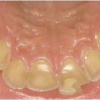

Hamba atritsioon

Atritsiooniks nimetame vastashammaste kontaktpindade patoloogilist kulumist. Tegemist võib olla nii üksiku hamba kuni kõigi hammaste kulumisega.

Hamba erosioon

Muu kui katubakterite happe põhjustatud hamba kõvakoe happelist kahjustust nimetatakse erosiooniks. Hape söövitab ehk demineraliseerib hambapinda, muutes selle pehmeks ja nii kiiresti kuluvaks.